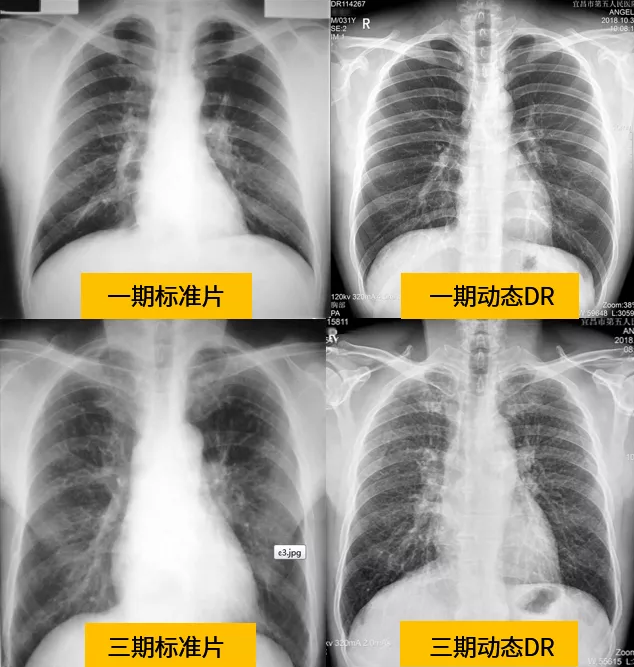

針對塵肺病在小陰影的特征和細節判斷上,傳統DR讀片誤差很難避免,也導致了對塵肺病期別的判斷誤差。由于各陰影間交叉重疊,不規則小陰影容易誤判為圓形小陰影。小陰影密集度完全靠讀片者憑工作經驗和比較標準片進行判斷,而標準片只反映了密集度的某個截面,當所讀片情況與標準片有差異時,則難以判斷。

與傳統DR設備不同,動態平板DR已不再局限于簡單的拍片功能,而是具有高清拍片、大幅面透視、高清點片、實時回放、自動曝光控制、全身拼接等多種功能。解決了傳統DR盲拍的劣勢,具有可視化操作功能,盡可能的避免誤診發生,極大的提高了診斷的準確性。